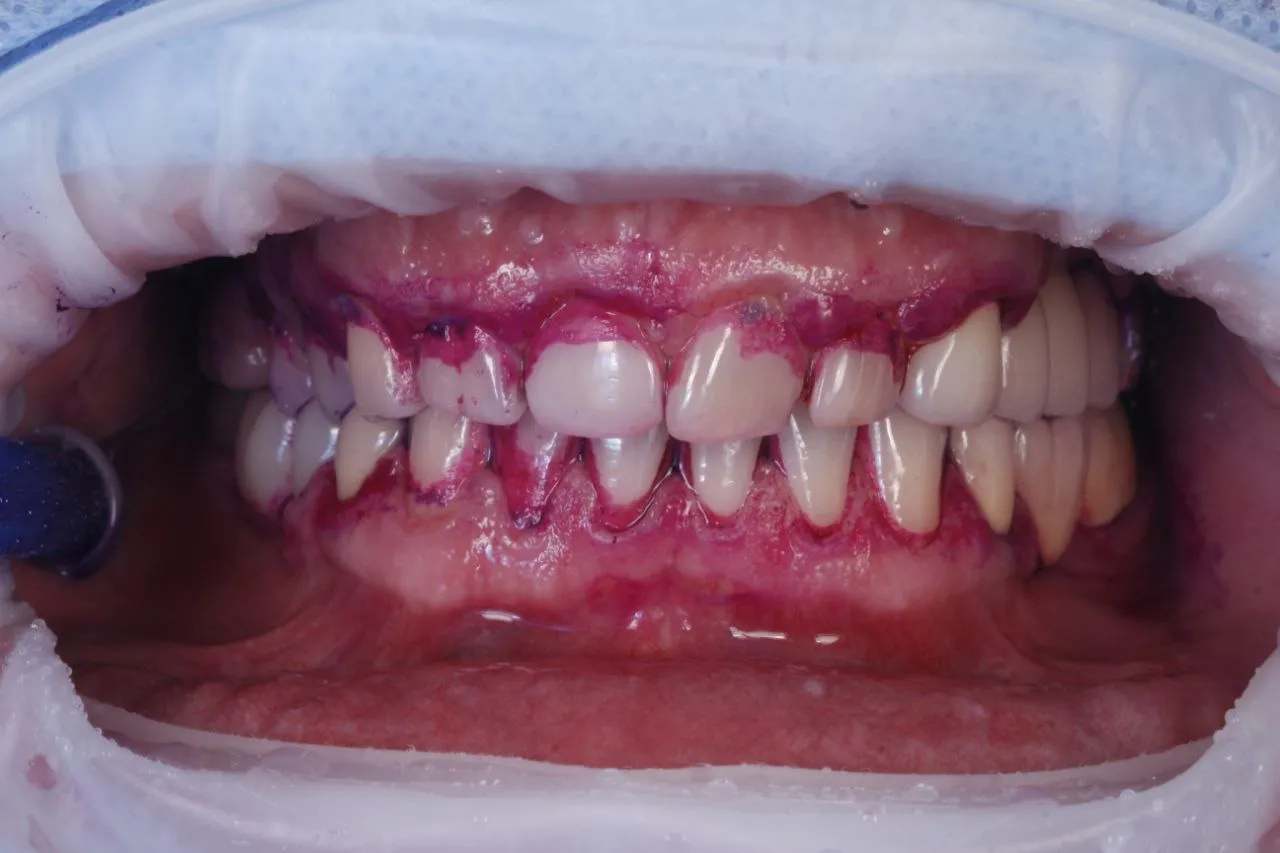

Професійна гігієна порожнини рота